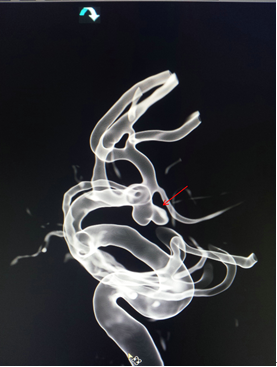

医生首先给李先生做了脑血管造影检查,如前所料,发现左侧前交通动脉瘤。神经内科张斌主任主持全科及神经外科张显强医师进行跨科室讨论,经积极的术前准备,决定急诊行颅内动脉瘤微弹簧圈介入栓塞术。介入手术在我院新引进的大型C臂飞利浦DSA机下完成。在张斌主任指导下,由张显强副主任医师主刀完成,术中发现动脉瘤约5mm大小,远端已形成破裂小泡,如不及时治疗,一旦再次破裂,后果不堪设想。经过1小时紧张的手术,在动脉瘤内填塞入4枚微弹簧圈,顺利结束手术。目前患者已康复出院,患者家属对治疗结果非常满意。

3D重建下的动脉瘤